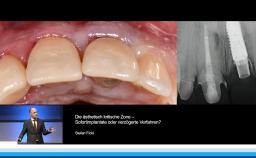

• die Wahl des idealen Implantationszeitpunktes in der ästhetisch kritischen Zone verstehen